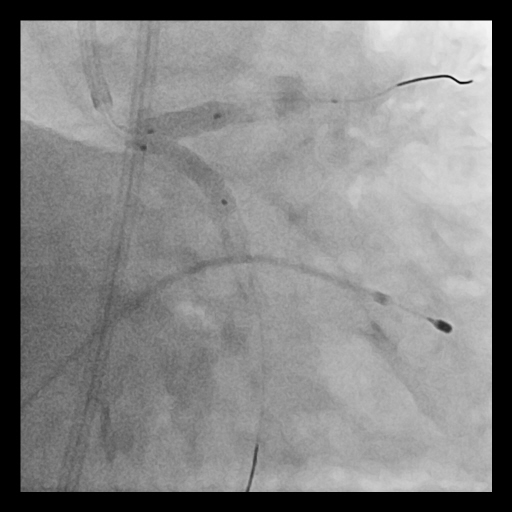

Coronary angiography showed long, tram-track dense calcification involving the left main bifurcation with subtotal occlusion of proximal LCx and diffuse proximal LAD disease. The calcified plaque exhibited significant radiopacities visible before contrast injection, suggesting a deep concentric calcium burden.

Given the extensive and concentric calcium across the LM bifurcation, an upfront ¡°Rotatripsy¡± strategy (rotational atherectomy followed by intravascular lithotripsy) was selected. A 1.25 mm burr was used for initial channel creation in the LCx and LM-LAD, with transient bradycardia requiring temporary pacing. Post-rotablation IVUS revealed residual deep calcium. Subsequently, intravascular lithotripsy (IVL) using a 3.5–4.0 mm balloon (1:1 sizing to proximal LCx and LM) was applied with 8 cycles, achieving clear calcium fracture on IVUS. Two DES were implanted sequentially (LCx: 3.5¡¿28 mm; LM–LAD: 4.0¡¿38 mm), followed by high-pressure post-dilation and final kissing balloon inflation. Final IVUS confirmed optimal stent expansion (MSA: LCx 7.7 mm©÷, LAD 12.1 mm©÷, LM 13.2 mm©÷) and well-apposed stents throughout the bifurcation.